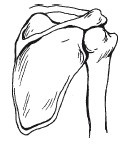

A mellkas tartalmaz 25 csontok: egy szegy - a szegycsont és a bordák 24. A felső hét pár borda van hátulján a gerinc, és az első - a szegycsont. A következő három pár egyesítjük csak a gerinc, és lekerekített elülső hogy a szegycsont. A két pár alsó úszó bordák nem is éri el az első része a mellkas. két kulcscsontból felett a bordák. Front, melyhez kapcsolódnak a szegycsont és a hátsó - a pengék. Minden kéz áll egy felkarcsont, és a két alkar csontjai - ulna és sugarát.

Váll (gömbcsukló)